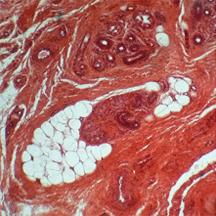

Aujourd'hui, le coffret renferme une collection de coupes histologiques réalisées en 1926 à l'Hôpital Saint Michel à Paris. Nous avons photographié quelques-unes de ces lames portant les fines tranches de tissus biologiques humains préparées à partir de prélèvements sur des patients. Nous ne sommes pas à même de reconnaître les zones médicalement intéressantes et, pour les photographies, nous avons privilégié le jeu des formes et des couleurs : c'est une façon de remarquer la qualité des préparations presque centenaires. Le microscope que nous avons utilisé est plus actuel que l'élégant "Nachet à pied anglais" recommandé, autrefois, pour les travaux d'histologie et de bactériologie. |

| Doigt (Dr J. Récamier - 1926) | Sein (Dr V. Pauchet - 1926) | ||||||||||||||||||||||||||||||||||||||||||||||||||||||||||||||||||||||||||||||||||||||||||||||||||||||||||||||||||||||||||||||||||||||||||||||||||||||||||||||||||||||||||||||||||||||||||||||||||||||||||||||||||||||||||||||||||||||||||||||||||||||||||||||||||||||||||||||||||||||||||||||||||||||||||||||||||||||||||||||||||||||||||||||||